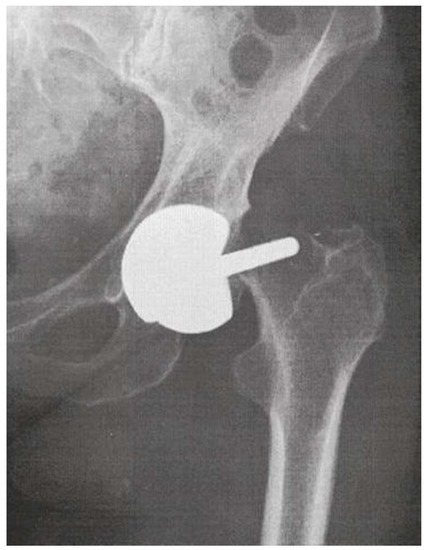

Metal-on-Metal (MoM) bearings for hip arthroplasty consisting of cobalt-chromium-molybdenum (CoCrMo) alloys were first introduced in the sixties by McKee and Farrar [1] and by Ring [2]. As early as 1968, Papps et al. published their findings on the toxicity of CoCrMo particles on tissue cultures [3], endorsed by the research of Trevor Rae, who, in 1979, concluded: ‘after the implantation of orthopaedic prostheses, metals can dissolve from the alloys used, some of the metals are toxic. […] From the biological standpoint, in view of the very much higher levels of soluble metal produced, metal against metal bearings should be avoided.’ [4] By that time, however, MoM hip arthroplasties had been abandoned for the low friction metal-on-polyethylene (MoP) hip replacements developed by Sir John Charnley [5]. When an increasing number of these MoP total hip arthroplasties (THA) had to be revised because of progressive loosening and extensive osteolysis caused by a macrophage response to polyethylene (PE) wear particles [6] whilst hip simulator studies were demonstrating substantially less volumetric wear from MoM bearing surfaces [7,8], MoM hip articulations were reintroduced to solve the problem of polyethylene (PE) particle-induced osteolysis. The imperfections regarding geometry, tolerance and metallurgy (low-carbon content associated with higher wear) of the first generation MoM articulations were resolved in the second generation high carbon content Metasul® MoM bearings (Sulzer/Centerpulse, Winterthur, Switzerland, 1988), which exhibited very promising short- and medium term results [9]. Furthermore, in the nineties, modern MoM hip resurfacing arthroplasty (HRA) (Figure 1) was proposed to address the inferior clinical results of THA in young and active patients, including the high dislocation rates of the 22 and 28 mm diameter femoral heads of the low friction MoP THA [10].

Figure 1.

Radiograph of a Metal-on-Metal (MoM) Hip Resurfacing Arthroplasty (HRA).